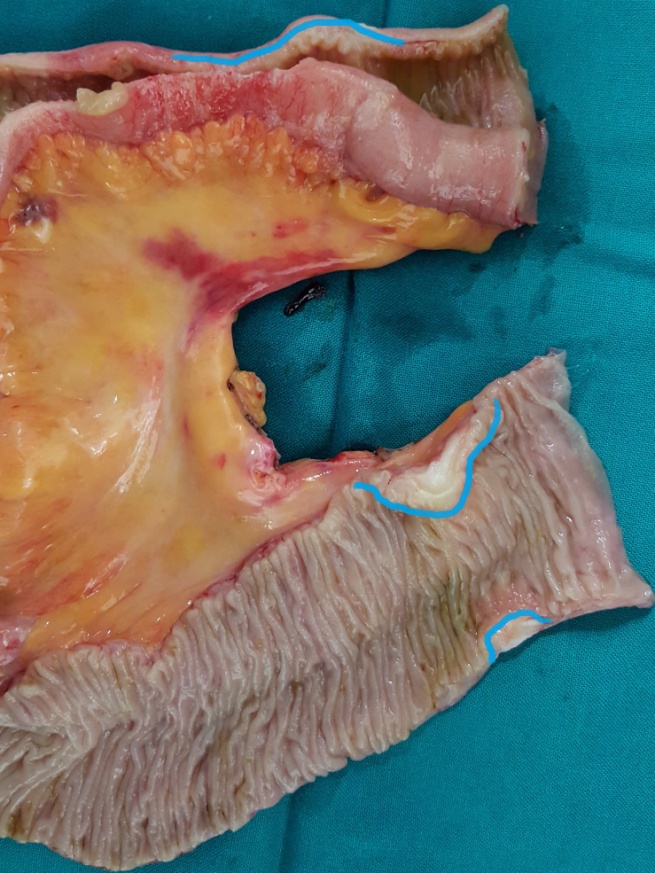

After opening the specimen, the metastatic foci are clearly visible (Courtesy Dr. V. Penopoulos)